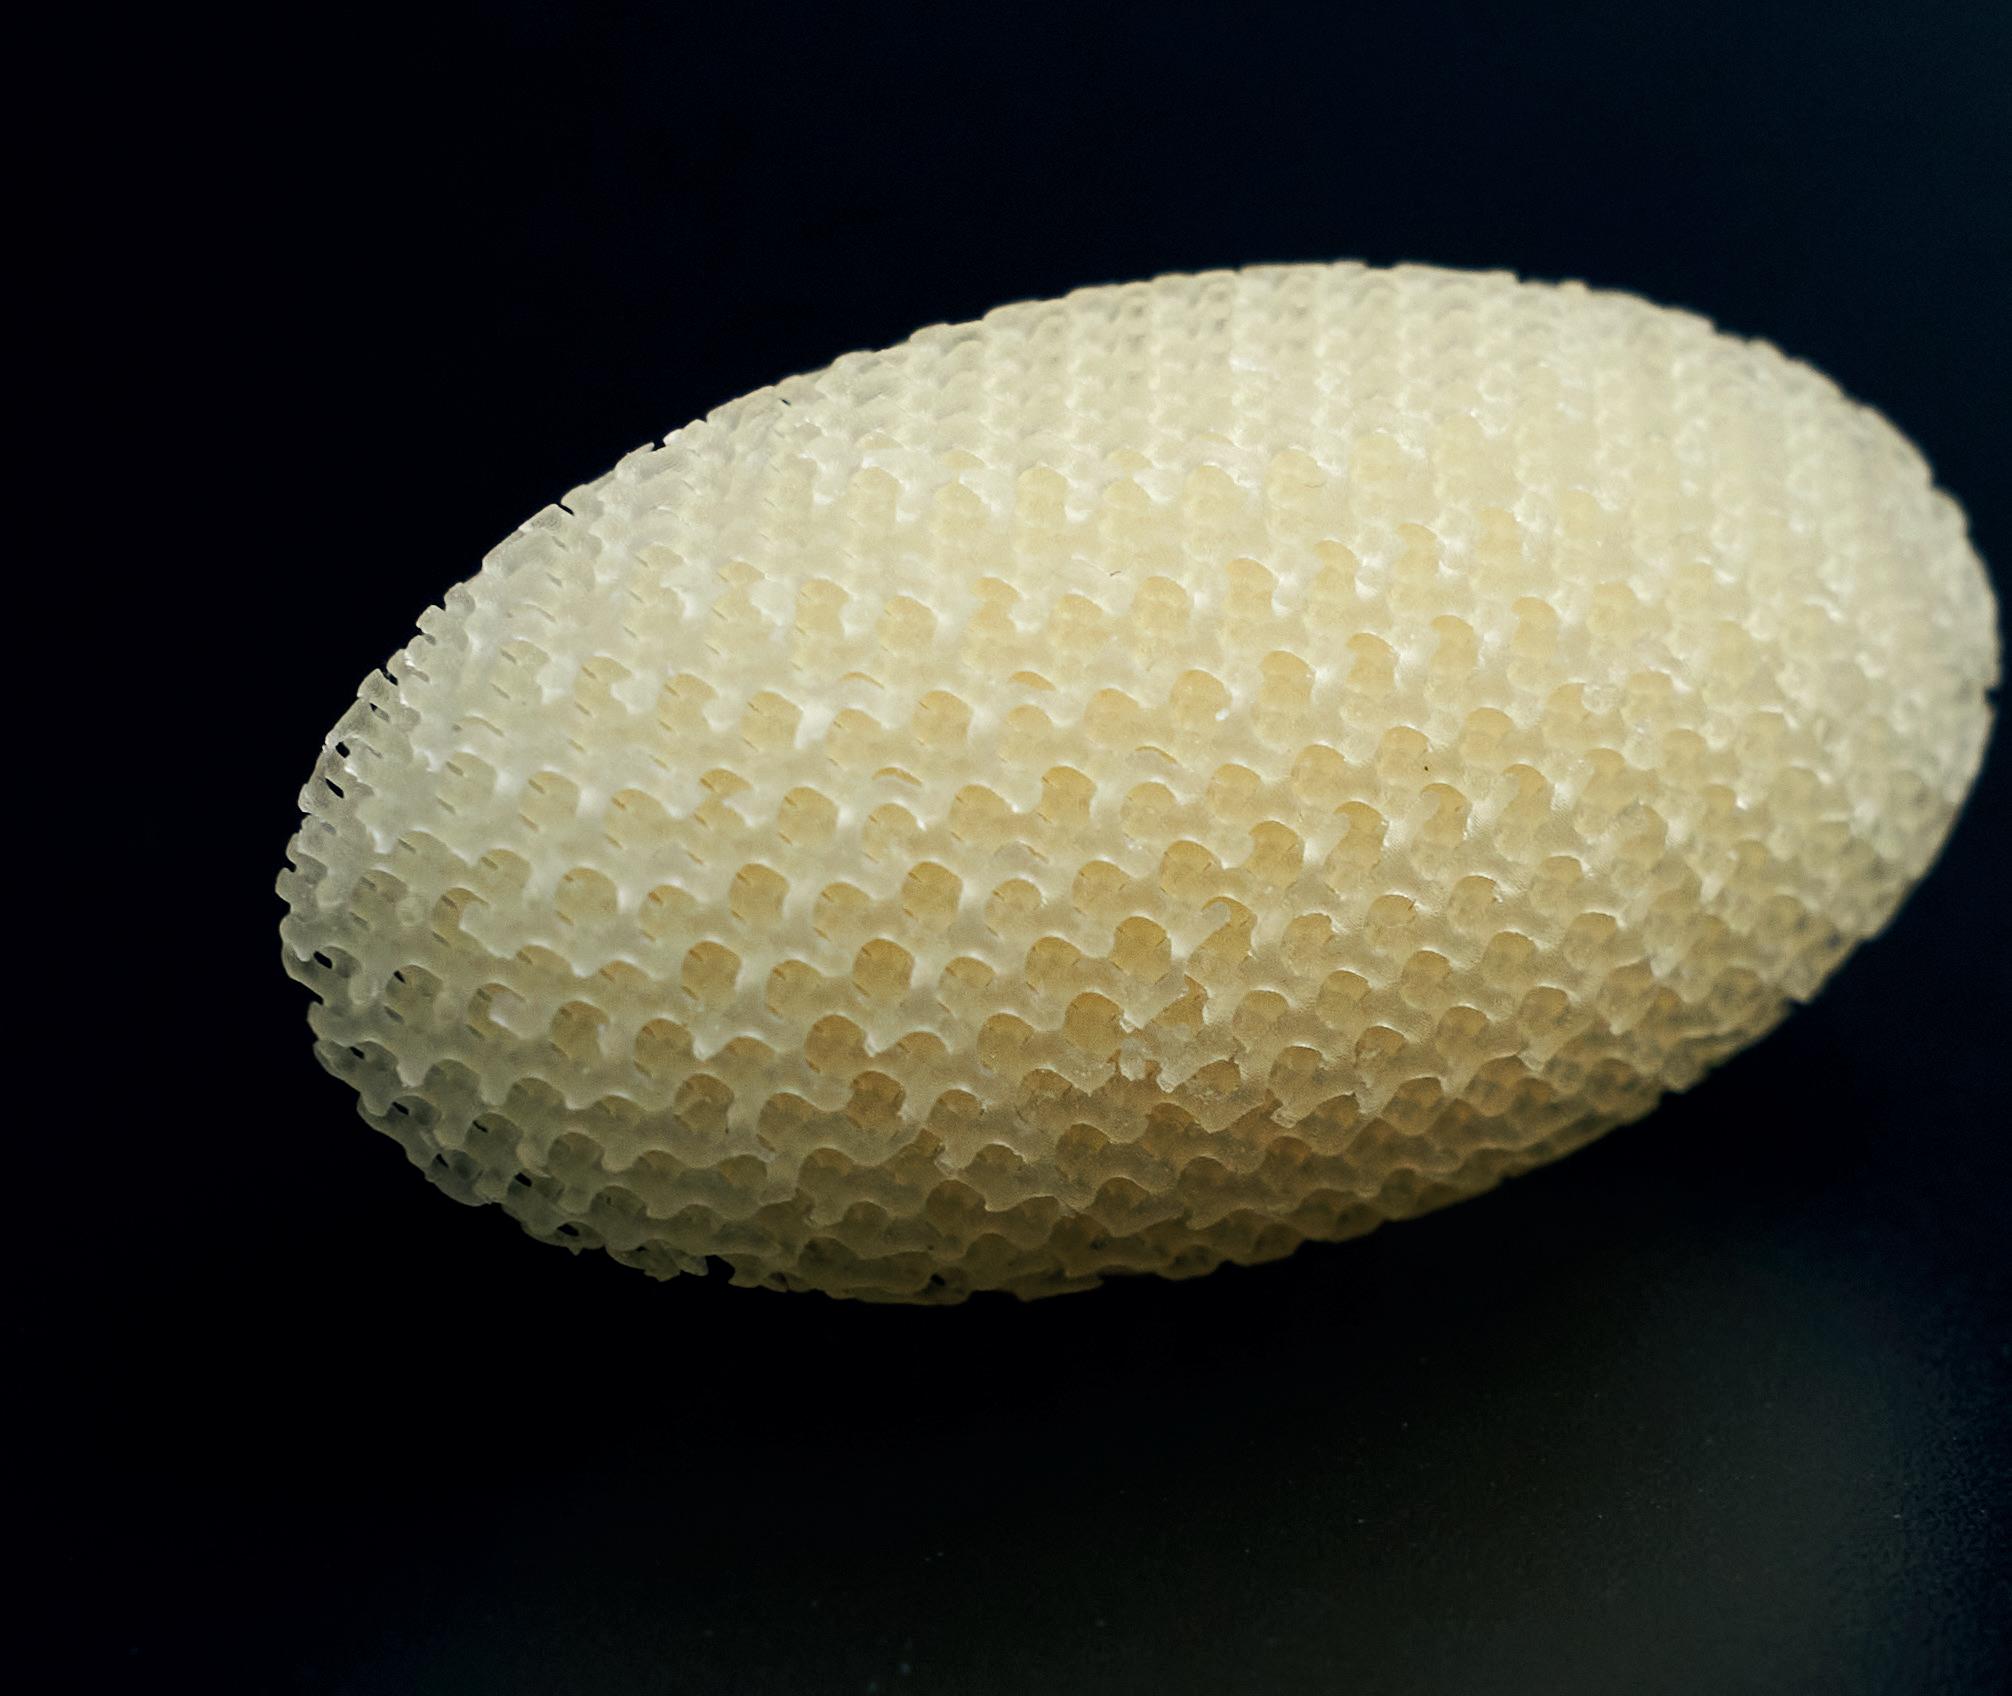

SHOWN: LUMPECTOMY DEVICE WITH SHAPE MEMORY LATTICE

reaction causing them to degrade from the inside out. That degradation can lead to a potentially very acidic local environment, which is not very good for tissue and that's a key drawback with those materials.” By contrast, 4Degra materials degrade via a progressive surface erosion process that stops the structure itself from collapsing suddenly. This means that any byproducts are also released much more gradually, resulting in reduced concentration levels. As tissue grows into the scaffold, this progressive erosion also improves the way the device itself is resorbed over time. 4D Biomaterials’ team of engineers and chemists is able to formulate the material for different needs. These can range from incredibly soft and flexible materials to those with rigid and strong properties. The company recently neighbored alongside TCT 3Sixty at the Med Tech Innovation Expo where an array of application examples, from 3D printed lattice structures for bone regeneration to microstructures for

SHOWN: 4DEGRA CAN BE FORMULATED FOR DIFFERENT APPLICATION REQUIREMENTS

splints, displayed the wealth of potential such material flexibility could bring. In one of the larger application examples, the materials were used to print a breast conserving lumpectomy device which is implanted into the void after the removal of a tumour. The device, printed in a soft tissue version of 4Degra, features a shape memory lattice structure and sponge-like quality, similar to breast tissue, so that it can be compressed into a smaller shape on implantation and then expand once it reaches body temperature. Over time, the patient’s natural tissue grows into the scaffold which will then degrade and be resorbed into the body. The device is said to have piqued the interest of breast surgeons in the U.S. who see this as a more efficient way of delivering better cosmetic outcomes without the need for reconstructive surgery.

In a different example featuring a stiffer material formulation, a lattice structure was applied to bridge the gap in a fracture and promote bone growth. For more complex cases, thanks to 3D printing, these kinds of devices can also be personalized.

“Those types of tissue scaffolds, with a very well-defined pore size and very high resolution, are great for growing tissue through,” Naylor added. “You couldn't make it any other way other than 3D printing.”